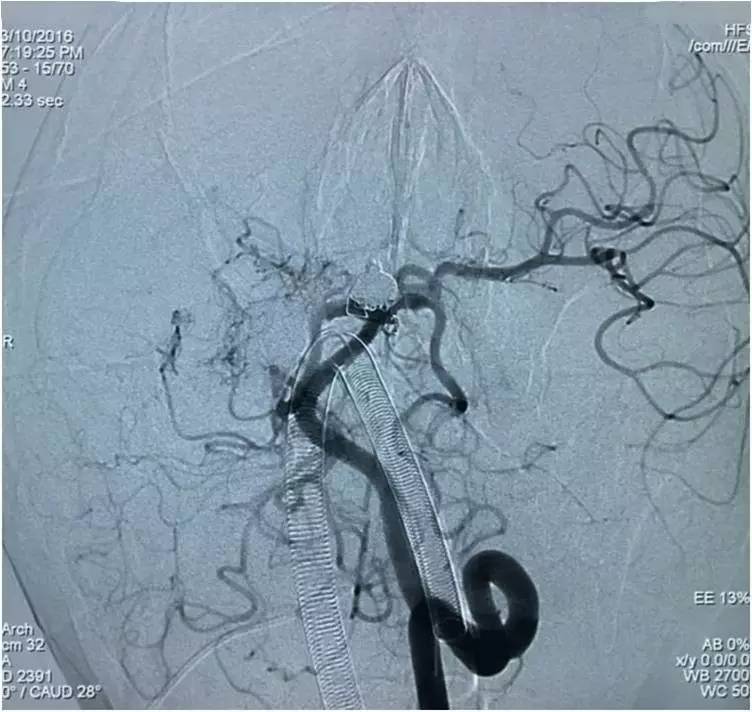

下面是术后各个角度的左椎动脉造影,可见基底动脉顶端动脉瘤和左小脑上动脉瘤完全栓塞,载瘤动脉畅通。基底动脉顶端动脉瘤的子瘤终于被消灭。

▼术后左椎动脉造影正位反汤28度。

▼纯正位。